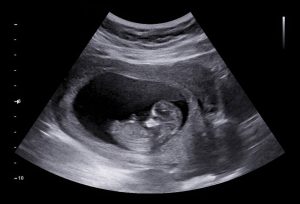

As there are those who say that Balling of the fetus in the fourth month On the right side is evidence that the mother will give birth to a boy, and therefore its concentration on the left side symbolizes that she will give birth to a girl. Doctors did not prove the validity of any of these sayings at all, as the gender of the newborn is accurately identified through ultrasound when his genitals are completed and he is seated. In a position that shows it to the doctor well.

Why does the fetus ball in the abdomen? There are many people who greatly link between flat stomach and the fact that the fetus is female, but this belief has no basis in truth at all, because doctors did not refer to this matter in any way, as it is the only known way through which it is possible to know the sex the fetus through ultrasound.